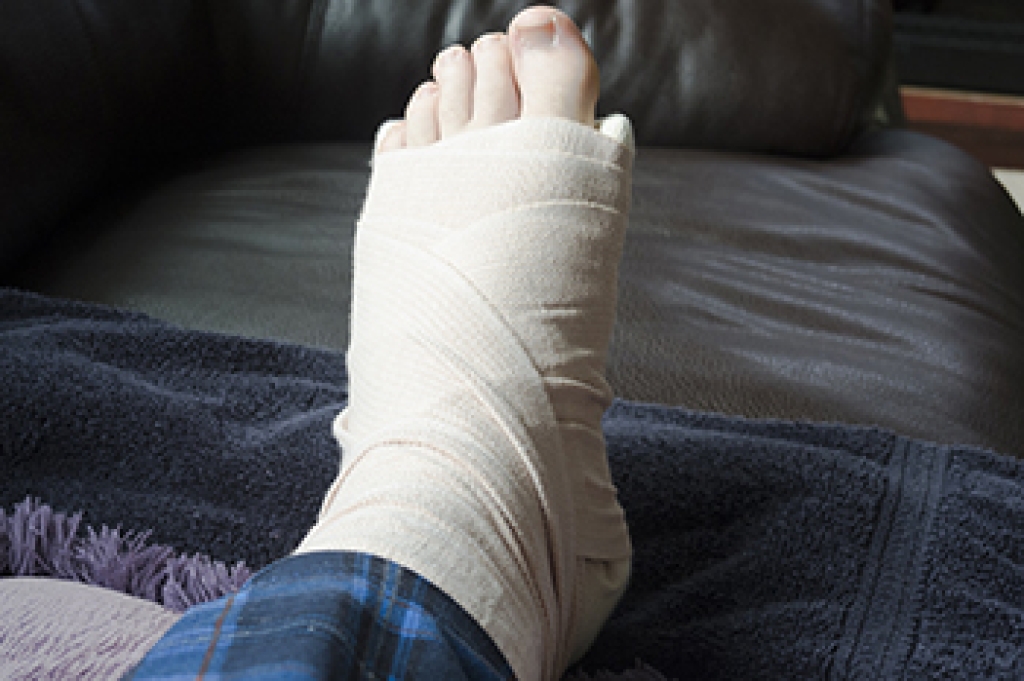

Treatment for broken bones varies depending on the cause, severity and location. Some will require the use of splints, casts or crutches while others could even involve surgery to repair the broken bones. Personal care includes the use of ice and keeping the foot stabilized and elevated.